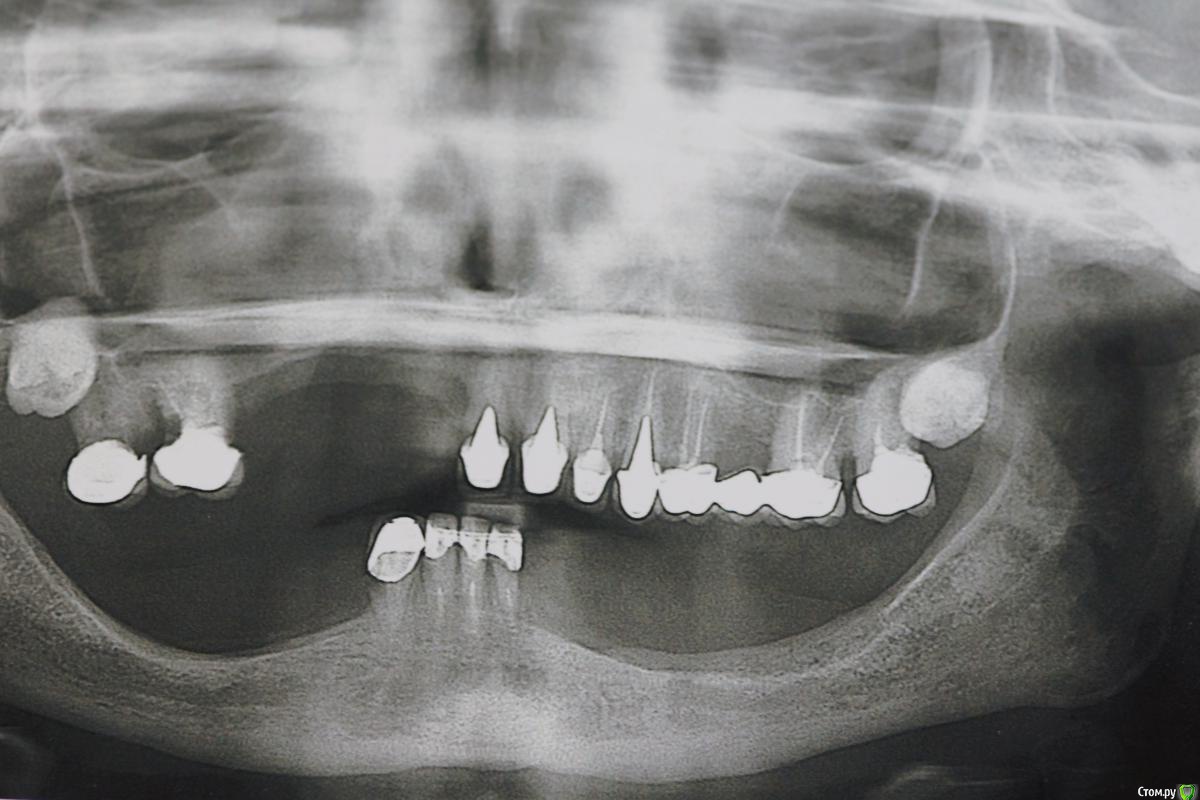

Dman Опубликовано 13 марта, 2019 Поделиться Опубликовано 13 марта, 2019 (изменено) Обратилась пациентка, панорама 2012 панорама 2018 Сейчас по ощущениям еще хуже Если с низом более или менее понятно, 4 винта и балка, чтобы разгрузить кость, то сверху вообще непонятно. Желание пациента жить и жевать. За эти 7 лет поменяли 7 съемных протезов, все они ей натирали и плохо держались. Анамнез чист, принимает только эстрогены Если есть кто-то из тольятти, кто готов взять пациента, с удовольствием передам контакты. Изменено 13 марта, 2019 пользователем Dman Ссылка на комментарий

колесников Опубликовано 13 марта, 2019 Поделиться Опубликовано 13 марта, 2019 Мне больше не нравится область 14-12. Чтобы сделать там красиво ,надо сильно постараться. И не раз. Ссылка на комментарий

АнтонТЛТ Опубликовано 13 марта, 2019 Поделиться Опубликовано 13 марта, 2019 Оценить зубы слева, удалить все зубы справа, через 2-3 мес аугментация с жёстким каркасом, через 6-8 мес имплантация 11,13,14,16, ещё через 4-6 мес фдм с восстановлением прикрепленных тканей, потом временное протезирование. Затем постоянное мостами 11-13 и 14-16. Ссылка на комментарий